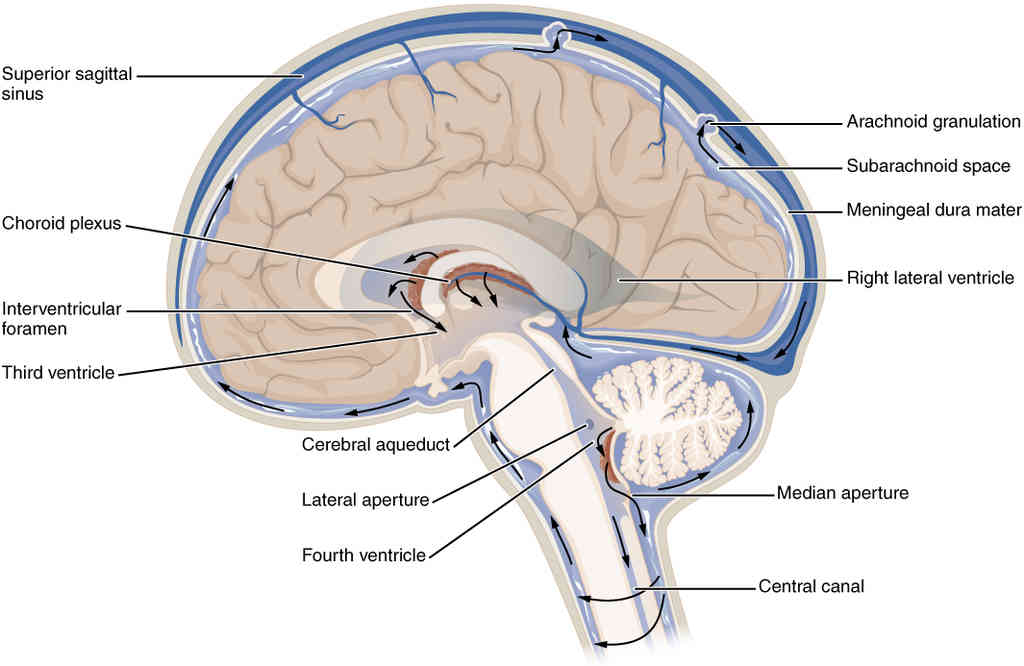

This page is under construction. For now, it is just a resource of the images found in the OpenStax Anatomy and Physiology Handbook. It wil slowly change into a revision tool. Each slide has a number. Use this to refer to the slide. When completed, it will have an unlabelled section, with labelled slides in parallel. On the unlabelled slides, write your answer and use the labelled slide to assess yourself. Keep track by also noting the number on each slide. Improvement at each attempt is important, more so than full marks on a first attempt.